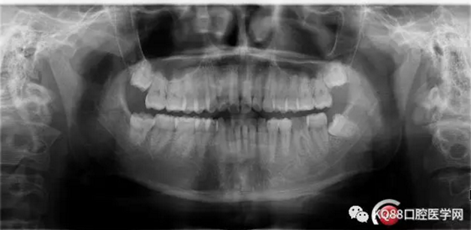

第五步:充填完成,ZOE暫時(shí)觀察。

9.png

10.png

充填完成,暫時(shí)觀察一周。下一步做牙冠延長,近遠(yuǎn)中打纖維樁,全冠或嵌體修復(fù)。